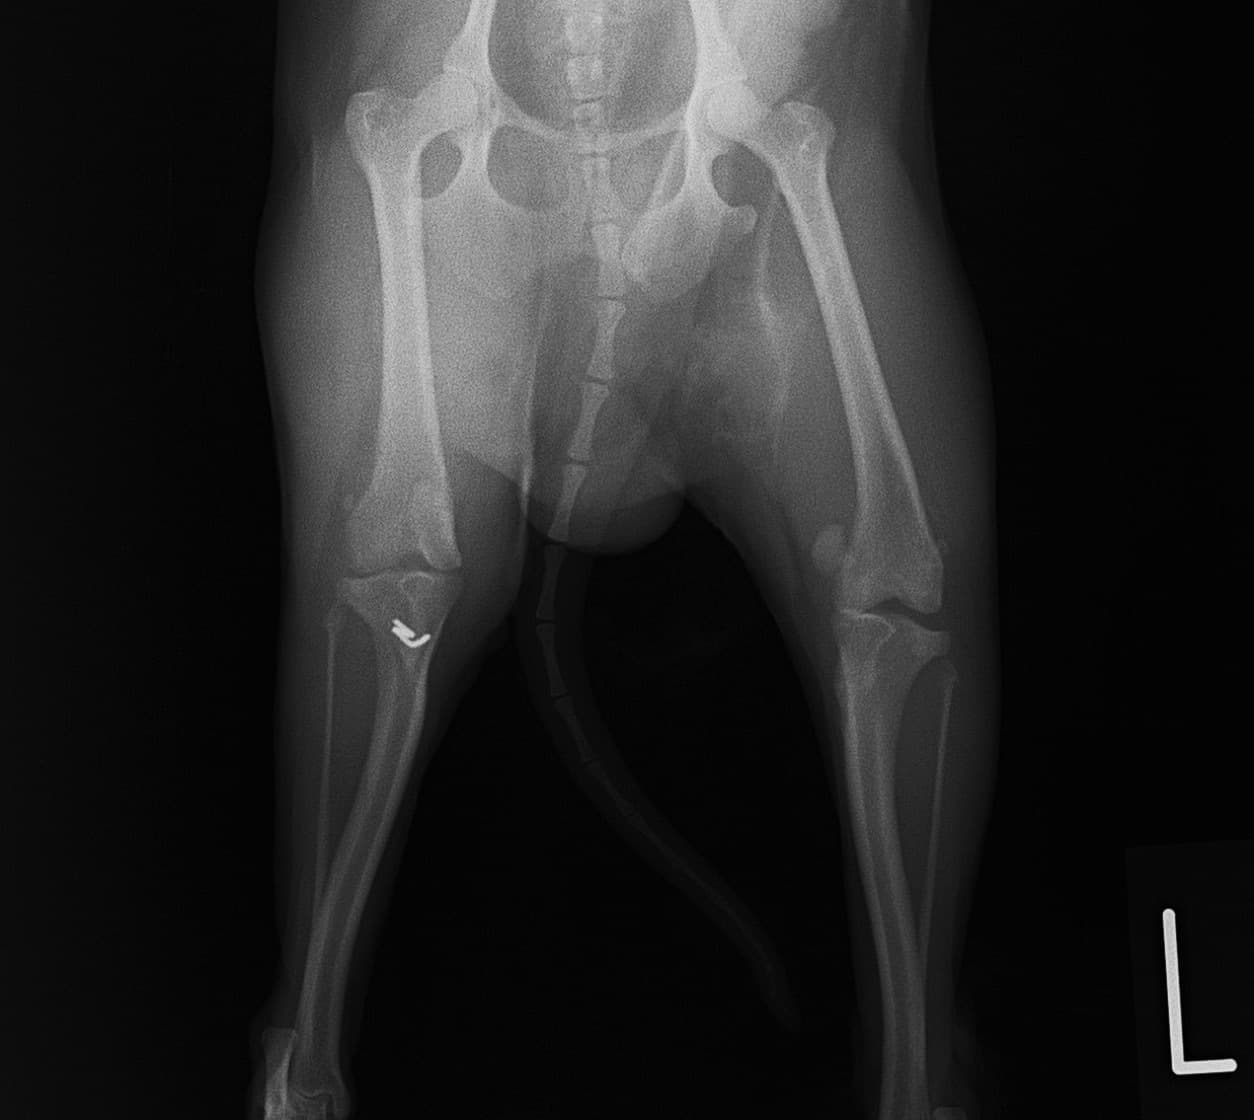

■ 症例20 ポメラニアン 8ヶ月 1.8kg

左右膝蓋骨脱臼 グレードⅢ

2ヶ月前から間欠的跛行が認められ、両膝の膝蓋骨脱臼整復術を行った。

手技は縫工筋及び内側広筋の解放、脛骨粗面の外側転位、滑車ブロック形造溝術、内外側関節包の縫縮を選択し実施した。

右側の膝蓋骨脱臼は上記手技で整復されたものの、左側はそれのみでは膝蓋骨が浮く様子が認められた。その為、PDS縫合糸にて膝蓋靱帯を1糸のみ縫合し、靱帯の縫縮を行った。

膝蓋骨脱臼は膝関節における膝蓋骨の内外側の脱臼と定義されるが、時として単純な内外の脱臼ではなく、膝蓋骨が大きく前方に浮き上がるように脱臼する場合がある。特にトイプードルやポメラニアンといった犬種に多く認められる。

内側脱臼に加えて前方への浮き上がりを矯正する為に、従来より脛骨粗面転移により膝蓋靭帯を外方と下方に引っ張り、固定する方法を選択する。膝蓋骨の前方への浮き上がりが軽度の場合は、従来法ではなく関節包の縫縮で対応していた。しかし、一部の症例で膝蓋骨の動きが悪くなり伸展機構が円滑に機能せずロボット様歩行になるケースがあった。

その為、膝蓋靭帯自体を縫縮する方法を採用した。この方法により、膝関節の伸展機構を妨げず膝蓋骨の軽度の浮きを矯正することが可能となった。

本症例の経過は良好である